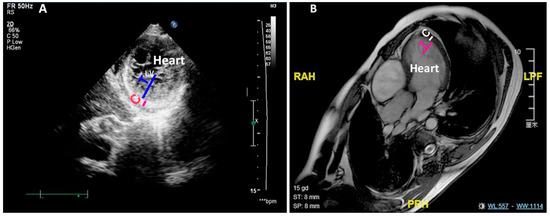

3.5. RVNC Does Not Associate with Reduced Contractility